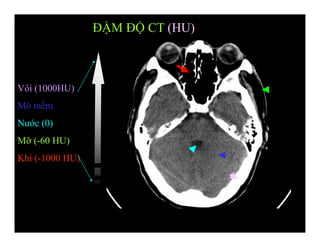

ĐẬM ĐỘ CT (HU)

Vôi (1000HU)

Mô mềm

Nước (0)

Mỡ (-60 HU)

Khí (-1000 HU)